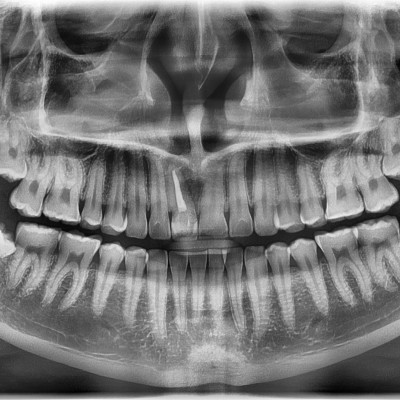

#18,28,38,48 사랑니 발치 #18,28,38,48 사랑니 발치 구강 외과 전문의가 당일 발치했습니다.

작성자 이턱이 작성일 01-28 조회 7